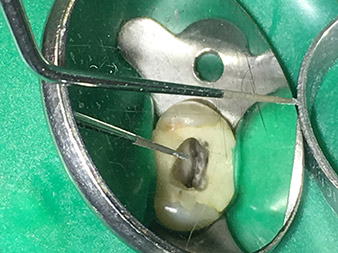

Speziell konzipiert für die Entfernung von abgebrochenen bzw. frakturierten Wurzelkanalinstrumenten ist die Spitze 3E. Meine Erfahrung hat gezeigt, dass dies im koronalen Bereich bis mittleren Kanalabschnitt mit einer entsprechenden Sichtvergrößerung (Lupe mind. 3,6-fach, besser Mikroskop) möglich ist.

Hier sollte mit einer nicht-diamantierten sehr spitz zulaufenden Spitze gearbeitet werden, mit der es möglich ist, unter dem Mikroskop die frakturierten Instrumentenfragmente im Dentinbereich freizupräparieren. Des Weiteren ist das Instrument sehr gut dazu geeignet, einen abgebrochenen Wurzelkanalstift koronal freizupräparieren, um ihn anschließend mit der Spitze 5E heraus zu vibrieren.

Ich verwende diese Spitze auch sehr oft dazu, um dünne Kanäle von Dentinüberhängen zu befreien und die Kanaleingänge darzustellen. Sie ist besonders gut geeignet z.B. beim zweiten mesiobukkalen Kanal bei den oberen Molaren oder bei verblockten Kanälen. Die Funktion bei dünnen Kanälen ist quasi analog zur Spitze 6E, die bei mittelgroßen bis dicken Kanalumfängen optimal arbeitet.